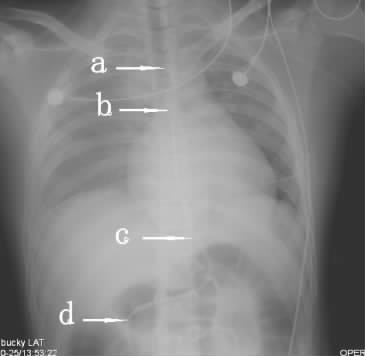

单中心双盲前瞻性研究。纳入研究的患者由一名具有成熟置管经验的住院医师采用常规盲插法置入鼻饲管,选复尔凯螺旋型鼻饲管(YZB/苏)内径CH10,长度145 cm(纽迪希亚医疗保健有限公司,荷兰)。超声法定位由另一名经过急危重症超声规范培训并有足够经验的临床医师(笔者本人)完成,操作前并不了解2种常规法定位的结果。患者取平卧位,使用Micro Maxx便携式超声机(SonoSite公司,美国)。颈部使用频率为6~13 MHz的直线线阵探头,在甲状腺峡部水平探查颈部,超声探头紧贴甲状腺左叶向中线区垂直扫查,食道横切面图像为规则圆形或椭圆形,不能被压扁、变形,内有空腔管道的回声或高回声的亮点,来回抽动鼻饲管时可见亮点回声移动。旋转探头获得食道长轴影像,可见鼻饲管的纵切面,为两条平行透亮高回声、呈“=”状。腹部换用频率为2~5 MHz的凸阵探头,在上腹部按照食道下段—贲门顺序探查鼻饲管,然后继续探查胃体—幽门、左腋中线处向中线区扫射胃底部查找,胃内可见两条平行透亮高回声、呈“=”形状的鼻饲管影像(图 1)。鼻饲管留置完毕2 h内进行床旁X线摄片,选用SM-50HF移动摄片机(赛德科公司,西班牙),由放射科技师按照规范获取胸部(含上腹部)的前后位摄片,放射科医师独立完成阅片并出具报告。结果判断参照英国NHS推荐的X线进行鼻饲管定位的标准[17](图 2)。

a:鼻饲管避开支气管轮廓沿食道方向下行;b:鼻饲管跨越气管隆突或支气管影像一直向下穿行;c:鼻饲管在身体中线位置穿越横膈进入膈下;d:在横膈下方鼻饲管末端清晰可见 图 2X线确定鼻饲管位置的方法